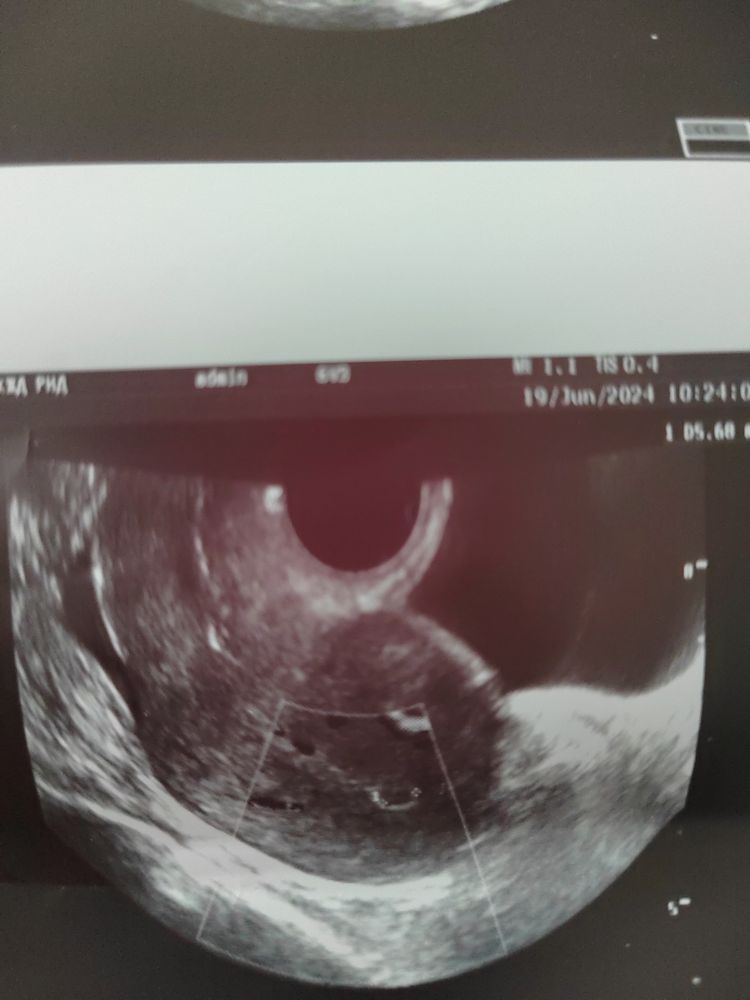

Вредная ), оказался полип , сегодня на 7 дц сделала узи